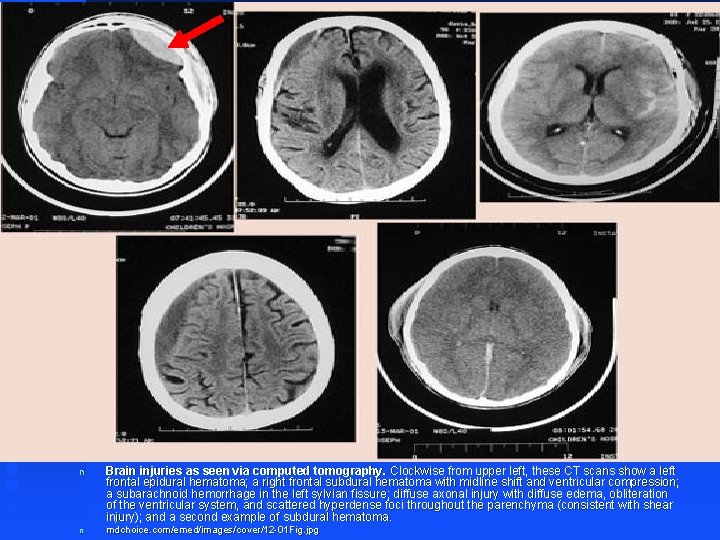

n Brain injuries as seen via computed tomography. Clockwise from upper left, these CT scans show a left frontal epidural hematoma; a right frontal subdural hematoma with midline shift and ventricular compression; a subarachnoid hemorrhage in the left sylvian fissure; diffuse axonal injury with diffuse edema, obliteration of the ventricular system, and scattered hyperdense foci throughout the parenchyma (consistent with shear injury); and a second example of subdural hematoma. n mdchoice. com/emed/images/cover/12 -01 Fig. jpg